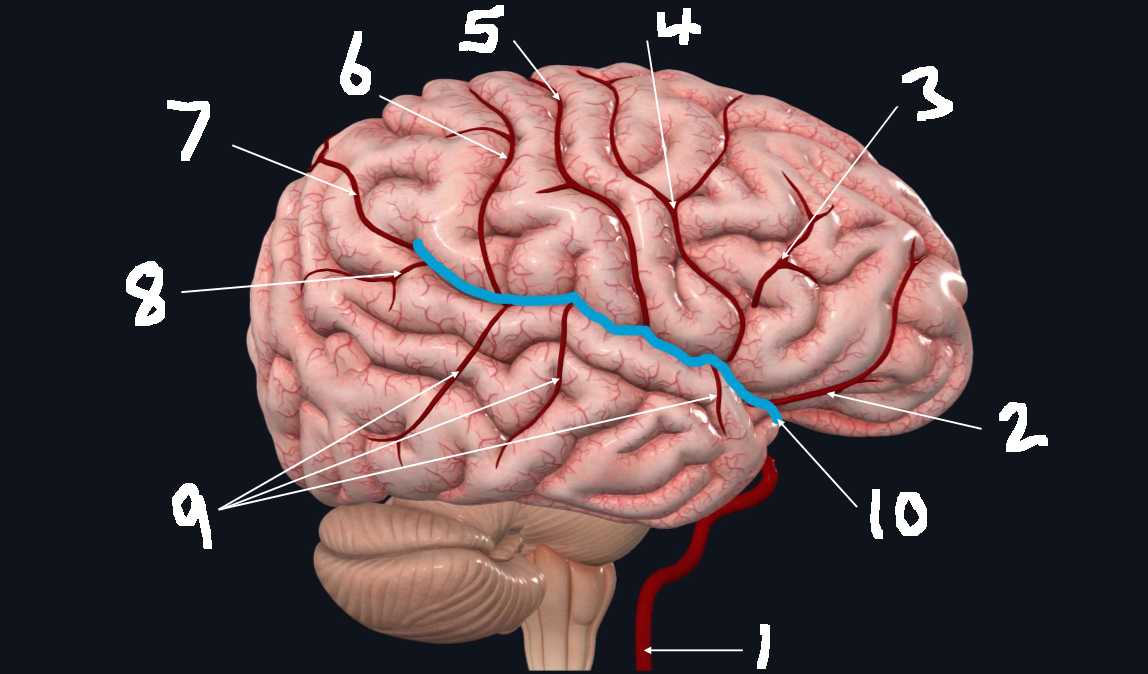

What is 1?

internal carotid artery

What is 2?

orbitofrontal artery

What is 3?

prefrontal artery

What is 4?

precentral artery

What is 5?

central artery

What is 6?

postcentral artery

What is 7?

posterior parietal artery

What is 8?

angular artery

What is 9?

temporal arteries (anterior, middle, posterior)

What is 10?

lateral cerebral fissure